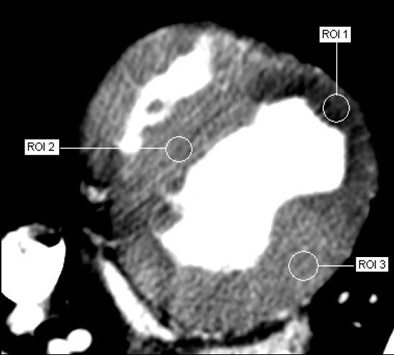

![]() |

| Adenosine-augmented 320-slice MDCT myocardial perfusion imaging provides semiquantitative measurements of myocardial perfusion. Image courtesy of Dr. Richard George and Dr. Albert Lardo, Johns Hopkins University. |

"Hopefully that perfusion study will be under 10 mSv, and that's what people are nervous about -- that this is going to change the game," he said.